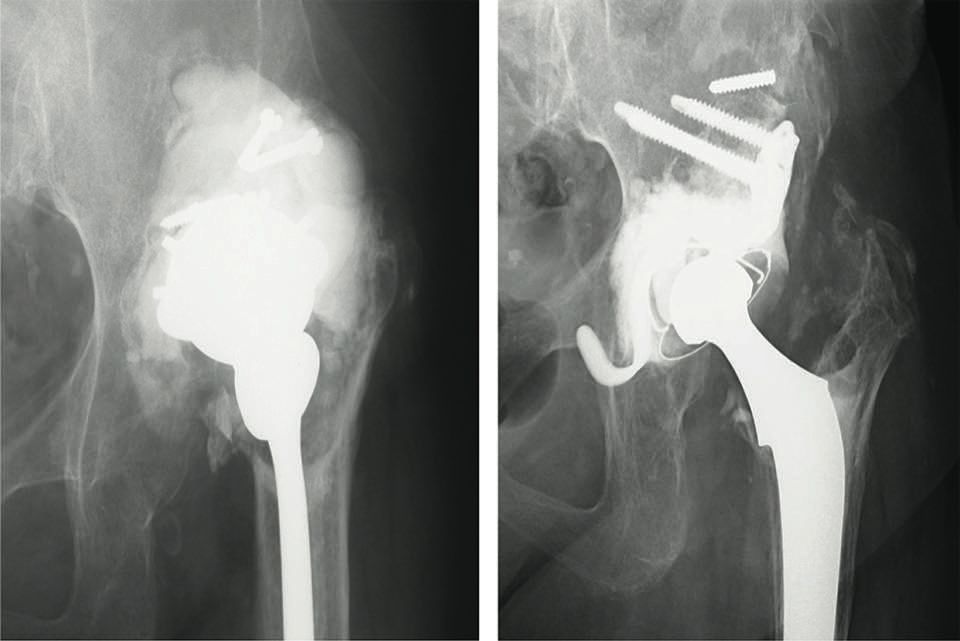

Indication: the KT cross is indicated for primary acetabular revisions with major bone loss, where the acetabulum has been badly damaged (e.g. rapidly destructive osteoarthritis of the hip (6)). Usually, revision hip replacements will use the anatomical acetabular location (Fig. 3).

The longer version of the device can be used to adjust the length of the limb in cases of a well-fixed stem, fixed pelvic obliquity and severe contracture. In Japan, osteoarthritis is commonly caused by developmental dysplasia of the hip (DDH). A higher cup location combined with a higher stem fixation is sometimes used for primary THR. For acetabular revisions, the cup is sometimes positioned slightly higher in order to adjust the length of the leg (Fig. 4).